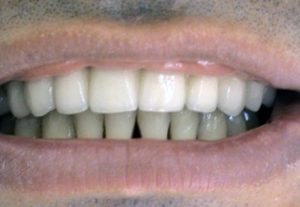

3. PHASE – prosthetic fabrication of temporary crown on implant

3. PHASE – fabrication of temporary solution